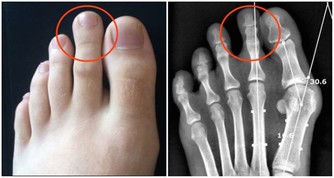

四肢浮腫脹脹的,特別是下半身,到晚上更明顯 不要傷腦筋,一起強力除濕以下簡單三招: